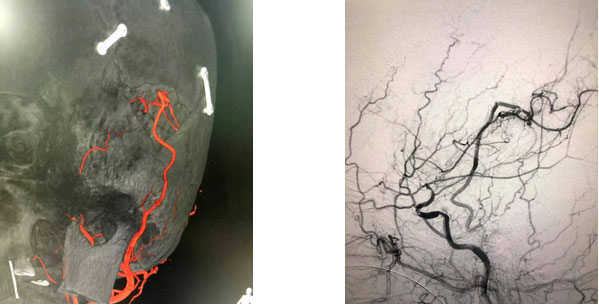

▲ 吻合口完美缝合

张琪博士在刘春医生和周林华医生协助下,在显微镜下将颅外颞浅动脉游离后引入颅内,与大脑中动脉分支行端侧吻合。由于吻合血管直径仅1mm左右,手术中在显微镜下使用仅有头发丝直径1/3的缝合线(10-0线)将吻合口缝合12针,才最终保证吻合口通畅并且无漏血。同时,进行硬脑膜翻转术。随后在复合手术室环境下,进行脑血管造影,显示搭桥血管血流通畅,颈动脉血流通畅,颈外动脉造影见颞浅动脉血流向受体动脉两端供血,搭桥手术成功,整个手术过程持续了5个多小时。

▲ 术后影像

术后,经过评估,患者脑血流得到明显改善,患者目前恢复良好,已经由术前浅昏迷状态慢慢清醒,并可以下床活动。